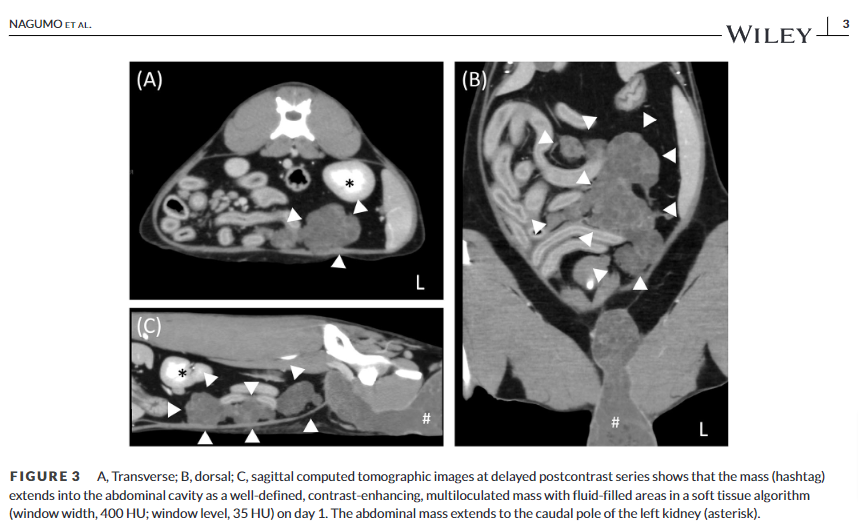

본 증례는 5세 수컷 고양이에서 발생한 고환 기형종에 대한 CT 영상 소견을 최초로 보고하고 있습니다. 주요 내용을 정리하면 다음과 같습니다.

- 고환 기형종의 CT 소견은 경도의 이질적 조영증강, 내부 석회화, 다방성 낭성 부위 등이 특징적입니다. 이는 다른 고환 종양(세르톨리세포종, 정상피종, 간질세포종)과 구별되는 소견입니다.